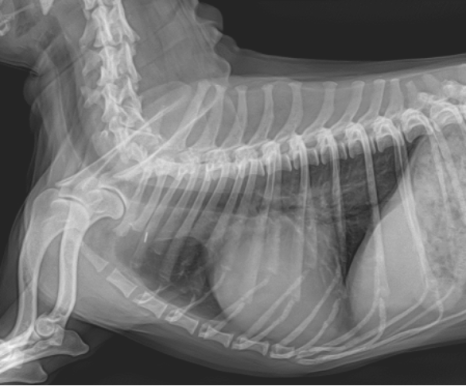

강아지 흉선 종양 제거 전(좌) / 흉선 종양 제거 후(우) / 출처: 양산에스동물메디컬센터